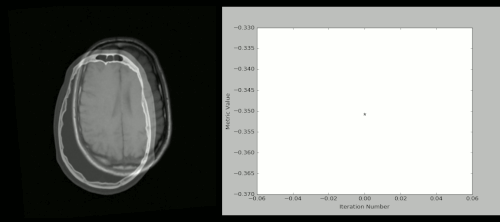

使用 Python + SimpleITK 实现的 CT/MR 图像配准过程:

SimpleITK animation